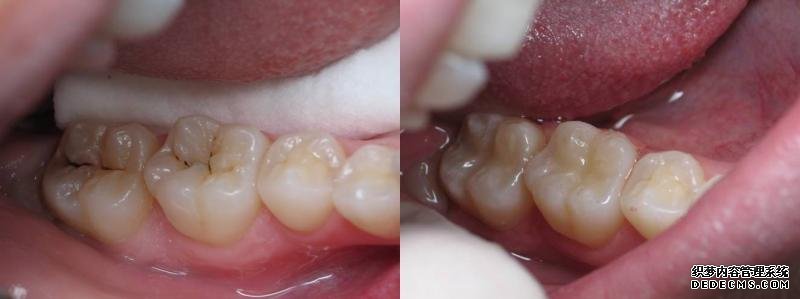

有虫牙怎么办?虫牙,又称“蛀牙”、“龋齿”,并不是牙齿中长了虫子,而是口腔中糖和酸共同作用,产生了致龋菌,腐蚀了牙体。虫牙是许多朋友都可能遇到的问题,根据第三次全国口腔健康流行病学调查结果显示,我国5岁儿童、35-44岁中青年、65-74岁老年人的龋齿率均超过了66%,65-74岁老年人更是高达98.4%。目前,临床上治疗虫牙最有效的方法就是补牙,同时越早治疗虫牙,效果越好。

一旦恒牙长了虫牙,就更应及时补牙了,这是因为恒牙一旦脱落了是无法再生的,另外,虫牙是一种破坏性的进行性疾病,不通过补牙是无法治愈的,而且虫牙不及时治疗,拖的时间越久,补牙难度越大。当虫牙导致牙体严重酸蚀缺损后,会直接侵袭牙髓或根尖周,导致剧烈牙疼,夜晚更甚,且伴有阵发性加剧的症状,这时有可能需要先进行根管治疗,清空髓腔和根管内的坏死物质再进行补牙填充,这样不仅增加了治疗难度、治疗费用,而且治疗时间也会延长。根管治疗通常需要2-4次才能完成。